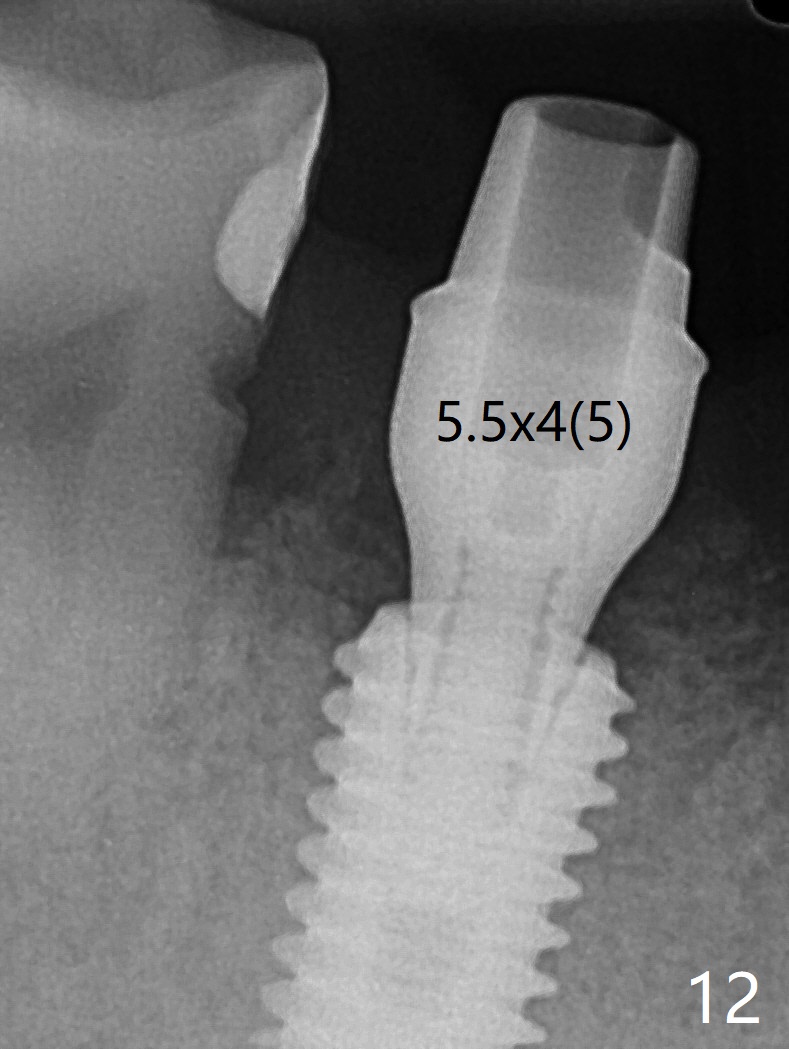

Although the tooth #30 has distobuccal root exposure (Fig.1 <), it is asymptomatic.  In contrast the tooth #31 with the distoocclusal caries (*) is symptomatic.  After use of 2 mm drill for 18 mm (lingual gingival margin), a calculated parallel pin is inserted (Fig.2 (D: 2 distal roots of the tooth #30)).  It appears that a 11.5 mm long implant is appropriate for the site; a 5 mm cuff is expected.  Following 4.8 mm drill, a 5.5x11.5 mm implant is placed initially (Fig.3) with an apical space (*) and clearance from the Inferior Alveolar Canal (red dashed line).  The implant is placed deeper with placement of a 6.5x4(5) mm abutment and bone graft (*, Fig.4,5).  After placement of collagen membrane over the graft, an immediate provisional is fabricated (Fig.6 P) with clearance from the opposing tooth (Fig.7 *).  There is no bone loss 3.5 months postop (Fig.8).  In fact the abutment has not been seated completely since its placement (Fig.4,5,8).  The crown/abutment dislodges 3 years 3 months post cementation (Fig.9).  The latter occurs for long incubation time because of opposing partial denture (Fig.10).  After trimming proximal surfaces (Fig.11: arrowheads), the abutment remains incompletely seated (Fig.11) due to possible crestal bone interference (Fig.11 *).  The smaller abutment by itself remains unseated (Fgi.12).  One size small one is completely seated (Fig.13).  Impression is taken.  Two weeks later the abutment margin is supragingival.  After screw torque at 20 Ncm, the crown is cemented with access hole.  Excess cement is removed.